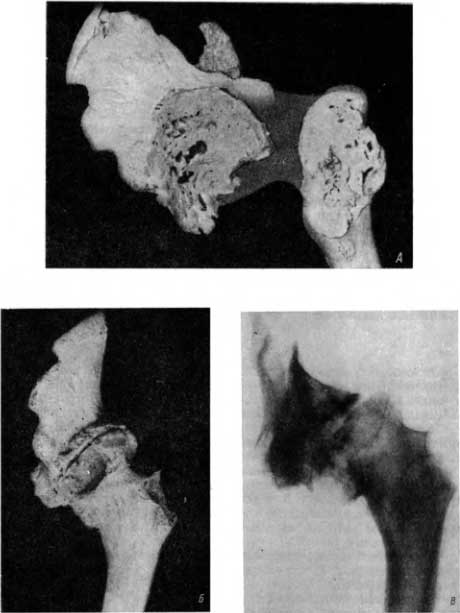

В погребении I–III вв. н. э. в городище Кобяково Ростовской области (раскопки С. И. Капошиной) были найдены кости тазобедренного сустава, на которых мы обнаружили следующие изменения. Кости были атрофированы, легки. Вертлужная впадина была разрушена почти на всем протяжении, в центральной ее части имелся круглый дефект (рис. 27, А). Крыша вертлужной впадины также подверглась деструкции на некотором протяжении. Значительная часть головки бедра была разрушена. В обнаруженной структуре головки видны 2 полости (рис. 27, А). Область деструкции «рыхлая», разреженная, без следов склероза.

Рис. 27. А — тяжелые деструктивные туберкулезные изменения в костях, участвующих в образовании тазобедренного сустава; Б — соотношения между указанными костями при их соединении; В — рентгенологически определяется только часть тяжелых изменений.

Бедренная кость, будучи соединена с тазовой, погружается в разрушенную вертлужную впадину таким образом, что головка и почти вся шейка не видны (рис. 27, Б).

На рентгенограмме с препарата, представленного на рис. 27, А (т. е. в условиях, приближающихся к клинико-рентгенологической практике), обнаруживается следующее: тяжелый деструктивный туберкулезный коксит с разрушением вертлужной впадины, головки и значительной части шейки бедренной кости, остеопороз и атрофия безыменной кости, атрофия и умеренный остеопороз бедренной кости, подвывих кверху (рис. 27, В). Имеющиеся полости в шейке бедра и вертлужной впадине, прорыв ее крыши на рентгенограмме не определяются. В погребении в Саркеле были обнаружены фрагменты тазобедренного сустава. Вертлужная впадина разрушена, перестроена, но в значительной мере покрыта новообразованной склерозированной костью. Имеется несколько ямок неправильной формы (рис. 28, А). В бедренной кости разрушена значительная, часть шейки. Область деструкции в значительной мере покрыта новообразованной склерозированной костью. Имеется несколько ямок на разрушенной поверхности.

Рис. 28. А — исход инфекционного коксита, наряду с деструкцией имеются реактивные склерозирующие изменения; Б — соотношения между указанными костями, „адаптация“ сохранившихся участков суставных поверхностей; В — рентгенологически доминируют реактивные склерозирующие изменения над деструкцией, в диафизе бедренной кости нет ни остеопороза ни атрофии.

При соединении оба фрагмента показывают отсутствие атрофии и определенное взаимное приспособление сочленяющихся частей (рис. 28, Б).

На рентгенограмме с препарата (рис. 28, В) определяется следующее. Деструкция ограничилась лишь поверхностными участками сочленяющихся костей. Имеется на значительном протяжении отчетливо выраженная склерозированная) замыкающая пластинка. Отсутствует атрофия; кости отличаются достаточной мощностью; картина инфекционного (возможно, гнойного) коксита (рис. 28, В) в фазе, близкой к исходу. Сохранившиеся на костных препаратах «ямы» (участки< более глубокой деструкции) на рентгенограмме не улавливаются.